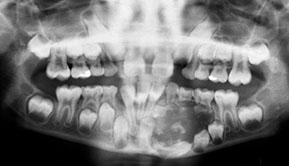

Dentigerous Cyst

- aka follicular cyst, odontogenic cyst

2nd MCC of odontogenic cyst (~1/5 epithelium-lined jaw cysts), and the MCC of developmental odontogenic cyst; usually in young adults and teens

- assoc c crown of an unerupted (or partially erupted) tooth, usually the mandibular third molars (wisdom teeth)

- thought that the pressure from an erupting tooth on the follicle obstructs venous flow and causes an exudate to form bwt the reduced enamel epithelium and the tooth crown

- multiple simultaneous cysts are uncommon

- may be found on radiographs taken for delayed tooth rupture; usually painless, can be painful if infected; can be large enough to displace involved teeth and cause resorption of adjacent teeth

Imaging: usually a well-defined, unilocular radiolucency on X-ray c sclerotic rim (can look the same as KCOT and ameloblastoma)

Micro: cyst cavity lined by stratified squamous epithelial cells from reduced enamel epithelium of the tooth forming organ

- has no rete ridges, flat interface, lining epithelium 2-4 layers of cuboidal epithelium

DDx: Cystic ameloblastoma (usually has reverse polarization of nuclei [away from BM]); KCOT (has hyperchromatic basal palisading of cuboidal / columnar cells, and wavy surface parakeratosis)

Px: excellent, almost never recur c complete enucleation

Dentigerous cyst lined b thin layer of stratified squames c chronic inflam in stroma